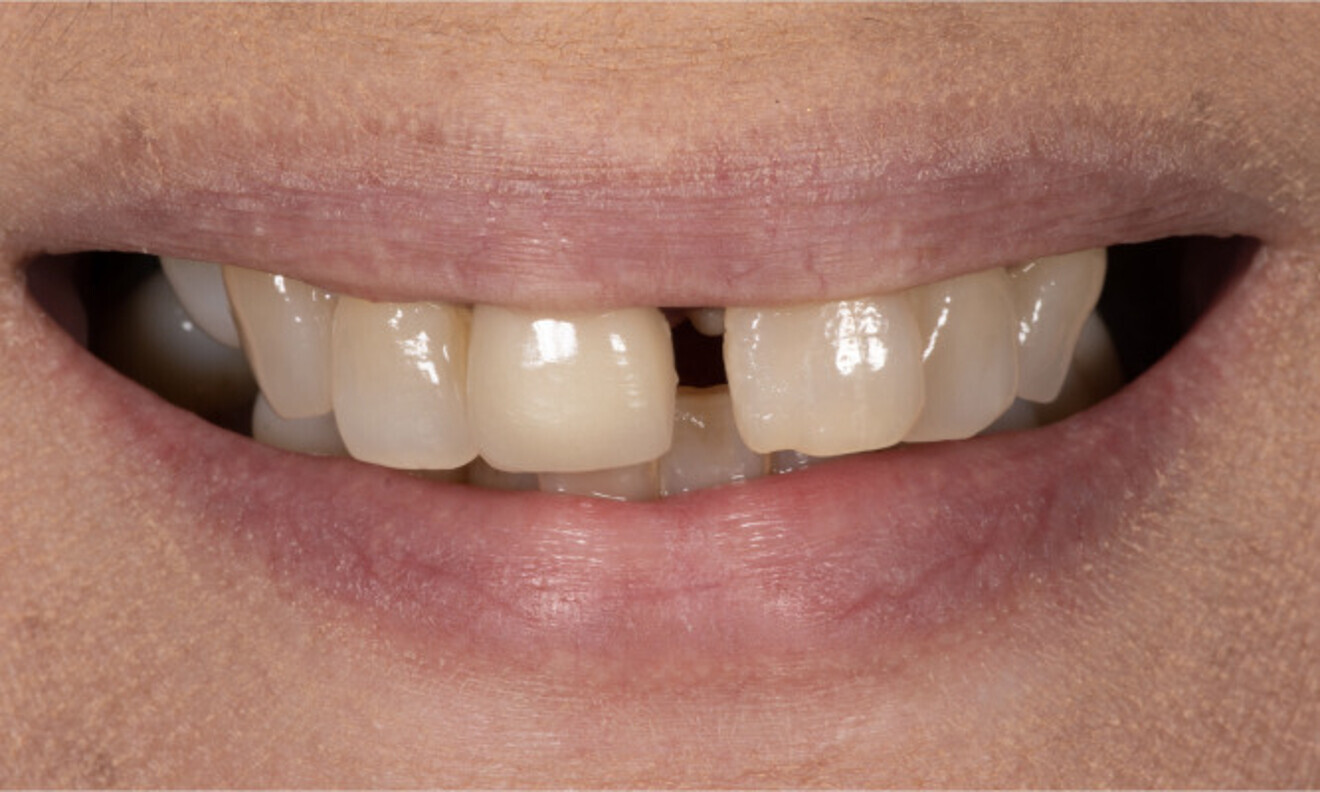

A 57-year-old female patient who was systemically healthy and a non-smoker and had no relevant medical history came to our clinic stating that she was unable to eat without pain and had absolutely no confidence or pride in her smile or overall appearance. She had also noticed flaring and progressive spacing of her anterior teeth and complained of food impaction. She desired a full-mouth fixed rehabilitation and wanted to improve the position of her teeth to regain the confidence to smile.

No abnormalities were found during the extra-oral examination. The patient presented with a low smile line. The intra-oral examination revealed terminal dentition due to generalised periodontal disease. The patient presented with severe resorption of the posterior maxilla bilaterally (Fig. 1). The radiographic examination showed generalised alveolar bone resorption with vertical bone defects (Fig. 2).